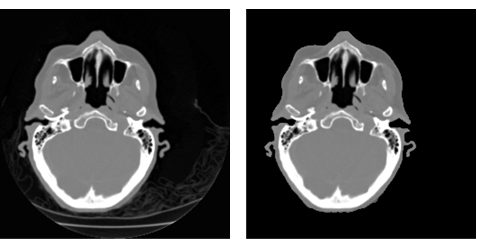

Use segmentation and segment selection techniques to remove the background features from an image. This would particularly be useful for volume reconstruction.

res = ImageMultiply[i, SelectComponents[FillingTransform@Binarize[i], "Area", -1]]; GraphicsRow[{i, res}]